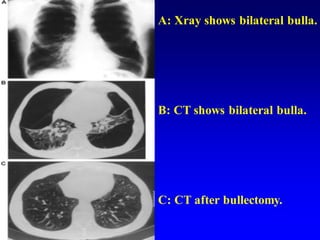

A: Xray shows bilateral bulla.

B: CT shows bilateral bulla.

C: CT after bullectomy.